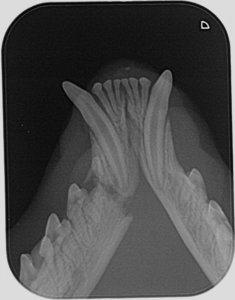

Kjevebrudd er en smertefull og alvorlig skade som krever korrekt behandling for å unngå alvorlige problemer senere i livet. Tenner som er involvert i frakturen kan bli betent og vil kreve behandling senere. Kjeven kan gro skjevt sammen og forårsake bittfeil eller man kan risikere at kjeven ikke gror sammen i det hele tatt. årsaken til kjevebrudd er som regel ytre traume, f.eks. bittskade eller en ulykke, men det kan også forårsakes av kreft, betennelse, periodontitt og andre sykdommer. Det er viktig å vurdere årsaken, pasientens alder og kliniske tilstand før man vurderer hvilken behandling man skal velge. Konvensjonelle kirurger foretrekker kanskje å stabilisere et kjevebrudd med plater og skruer. Dette kommer ofte i konflikt med tannstrukturer og kan dermed forårsake nye problemer som kan være vanskelig å rette opp i senere. Hos Dyretannklinikken vil vi alltid velge den behandling som er mest skånsom for pasienten, men samtidig gir det beste resultatet med tanke på unngå fremtidige komplikasjoner.